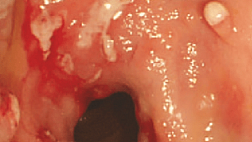

При эндоскопическом исследовании в случае бронхоэктазов в стадии ремиссии выявляется

частично диффузный бронхит I степени воспаления